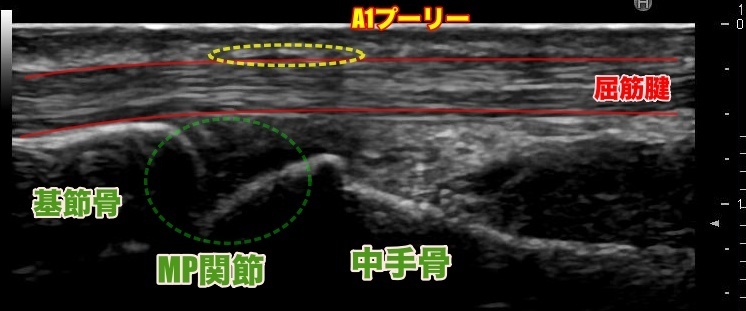

指が引っかかる症状が出ますが、指の付け根である【A1プーリー】という場所で引っかかりが起き、押すと痛みがあります。

US(超音波検査)

超音波で、実際に引っかかりの部位を確認し、周囲の腫れや滑走が悪い場所・実際に引っかかっている像などを確認します。

当院では、出来る限り少量で、ピンポイントで効果が出る様に、超音波ガイド下で1mm単位で調整して注射を行います。